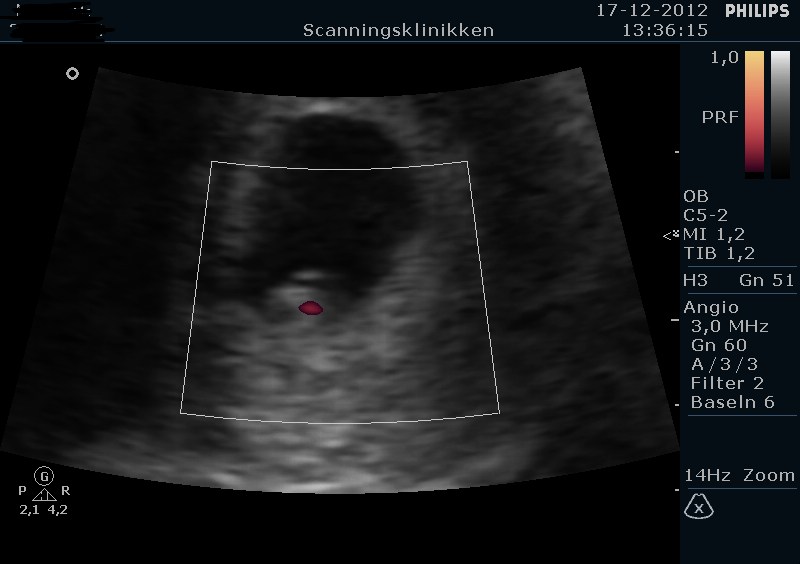

Så har jeg været til tidlig tryghedsscanning i dag - selv betalt selvfølgelig

Jeg blev sat én dag frem så den hedder 7+3 i stedet for 7+2 lige pt. Det kan jo sagtens nå at ændre sig

Jeg gik selvfølgelig lidt i panik i morges da der var en meget lille smule blod på papiret, så man kan vel sige held i uheld at vi skulle ind i dag. Heldigvis lå der en fin lille peanut derinde med flot hjerteblink, så det var super dejligt

Vedhæfter lige billeder